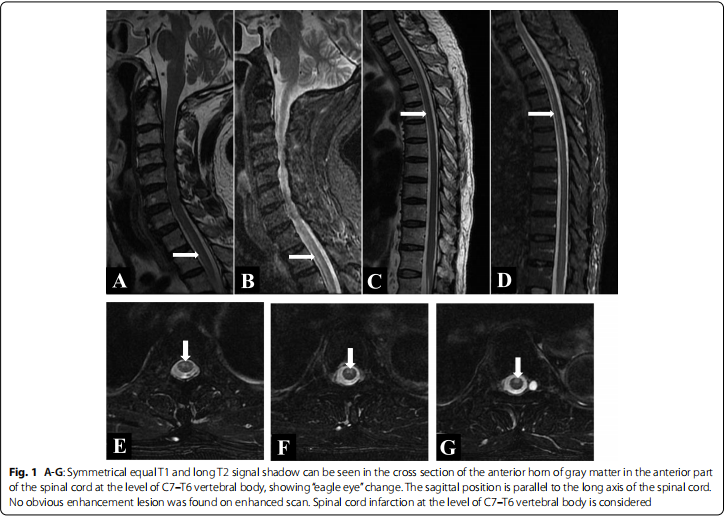

病例2:《Long-segment spinal cord infarction complicated with multiple cerebral infarctions: a case report》发表于《BMC Neurology》杂志(IF 2.9)。患者是一名65岁男性,因“双下肢无力11小时”到我院就诊。患者在卸重物时突然出现胸部、背部和上肢剧烈疼痛,随后出现双下肢瘫痪。入院后完善脊髓MR检查提示C7至T6水平脊髓梗死,颅脑MR检查提示双侧基底节区、放射冠区多发急性脑梗死,经过积极治疗后,患者双下肢肌力逐渐恢复,出院后3个月随访时患者可借助助行器行走。本病例的罕见之处在于患者脊髓梗死的节段长,累及C7至T6节段,目前国际上暂未见报道过累及8个脊髓节段的梗死,同时本例患者出现长节段脊髓梗死合并颅内多发急性梗死的病因也值得进一步探讨。

脊髓MR增强提示C7-T6椎体水平的脊髓梗死